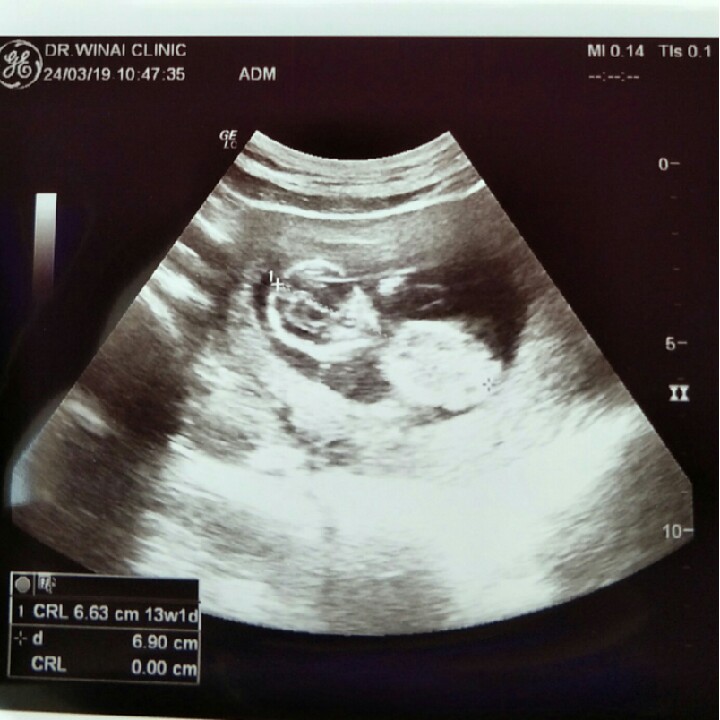

13 วัคค่ะ